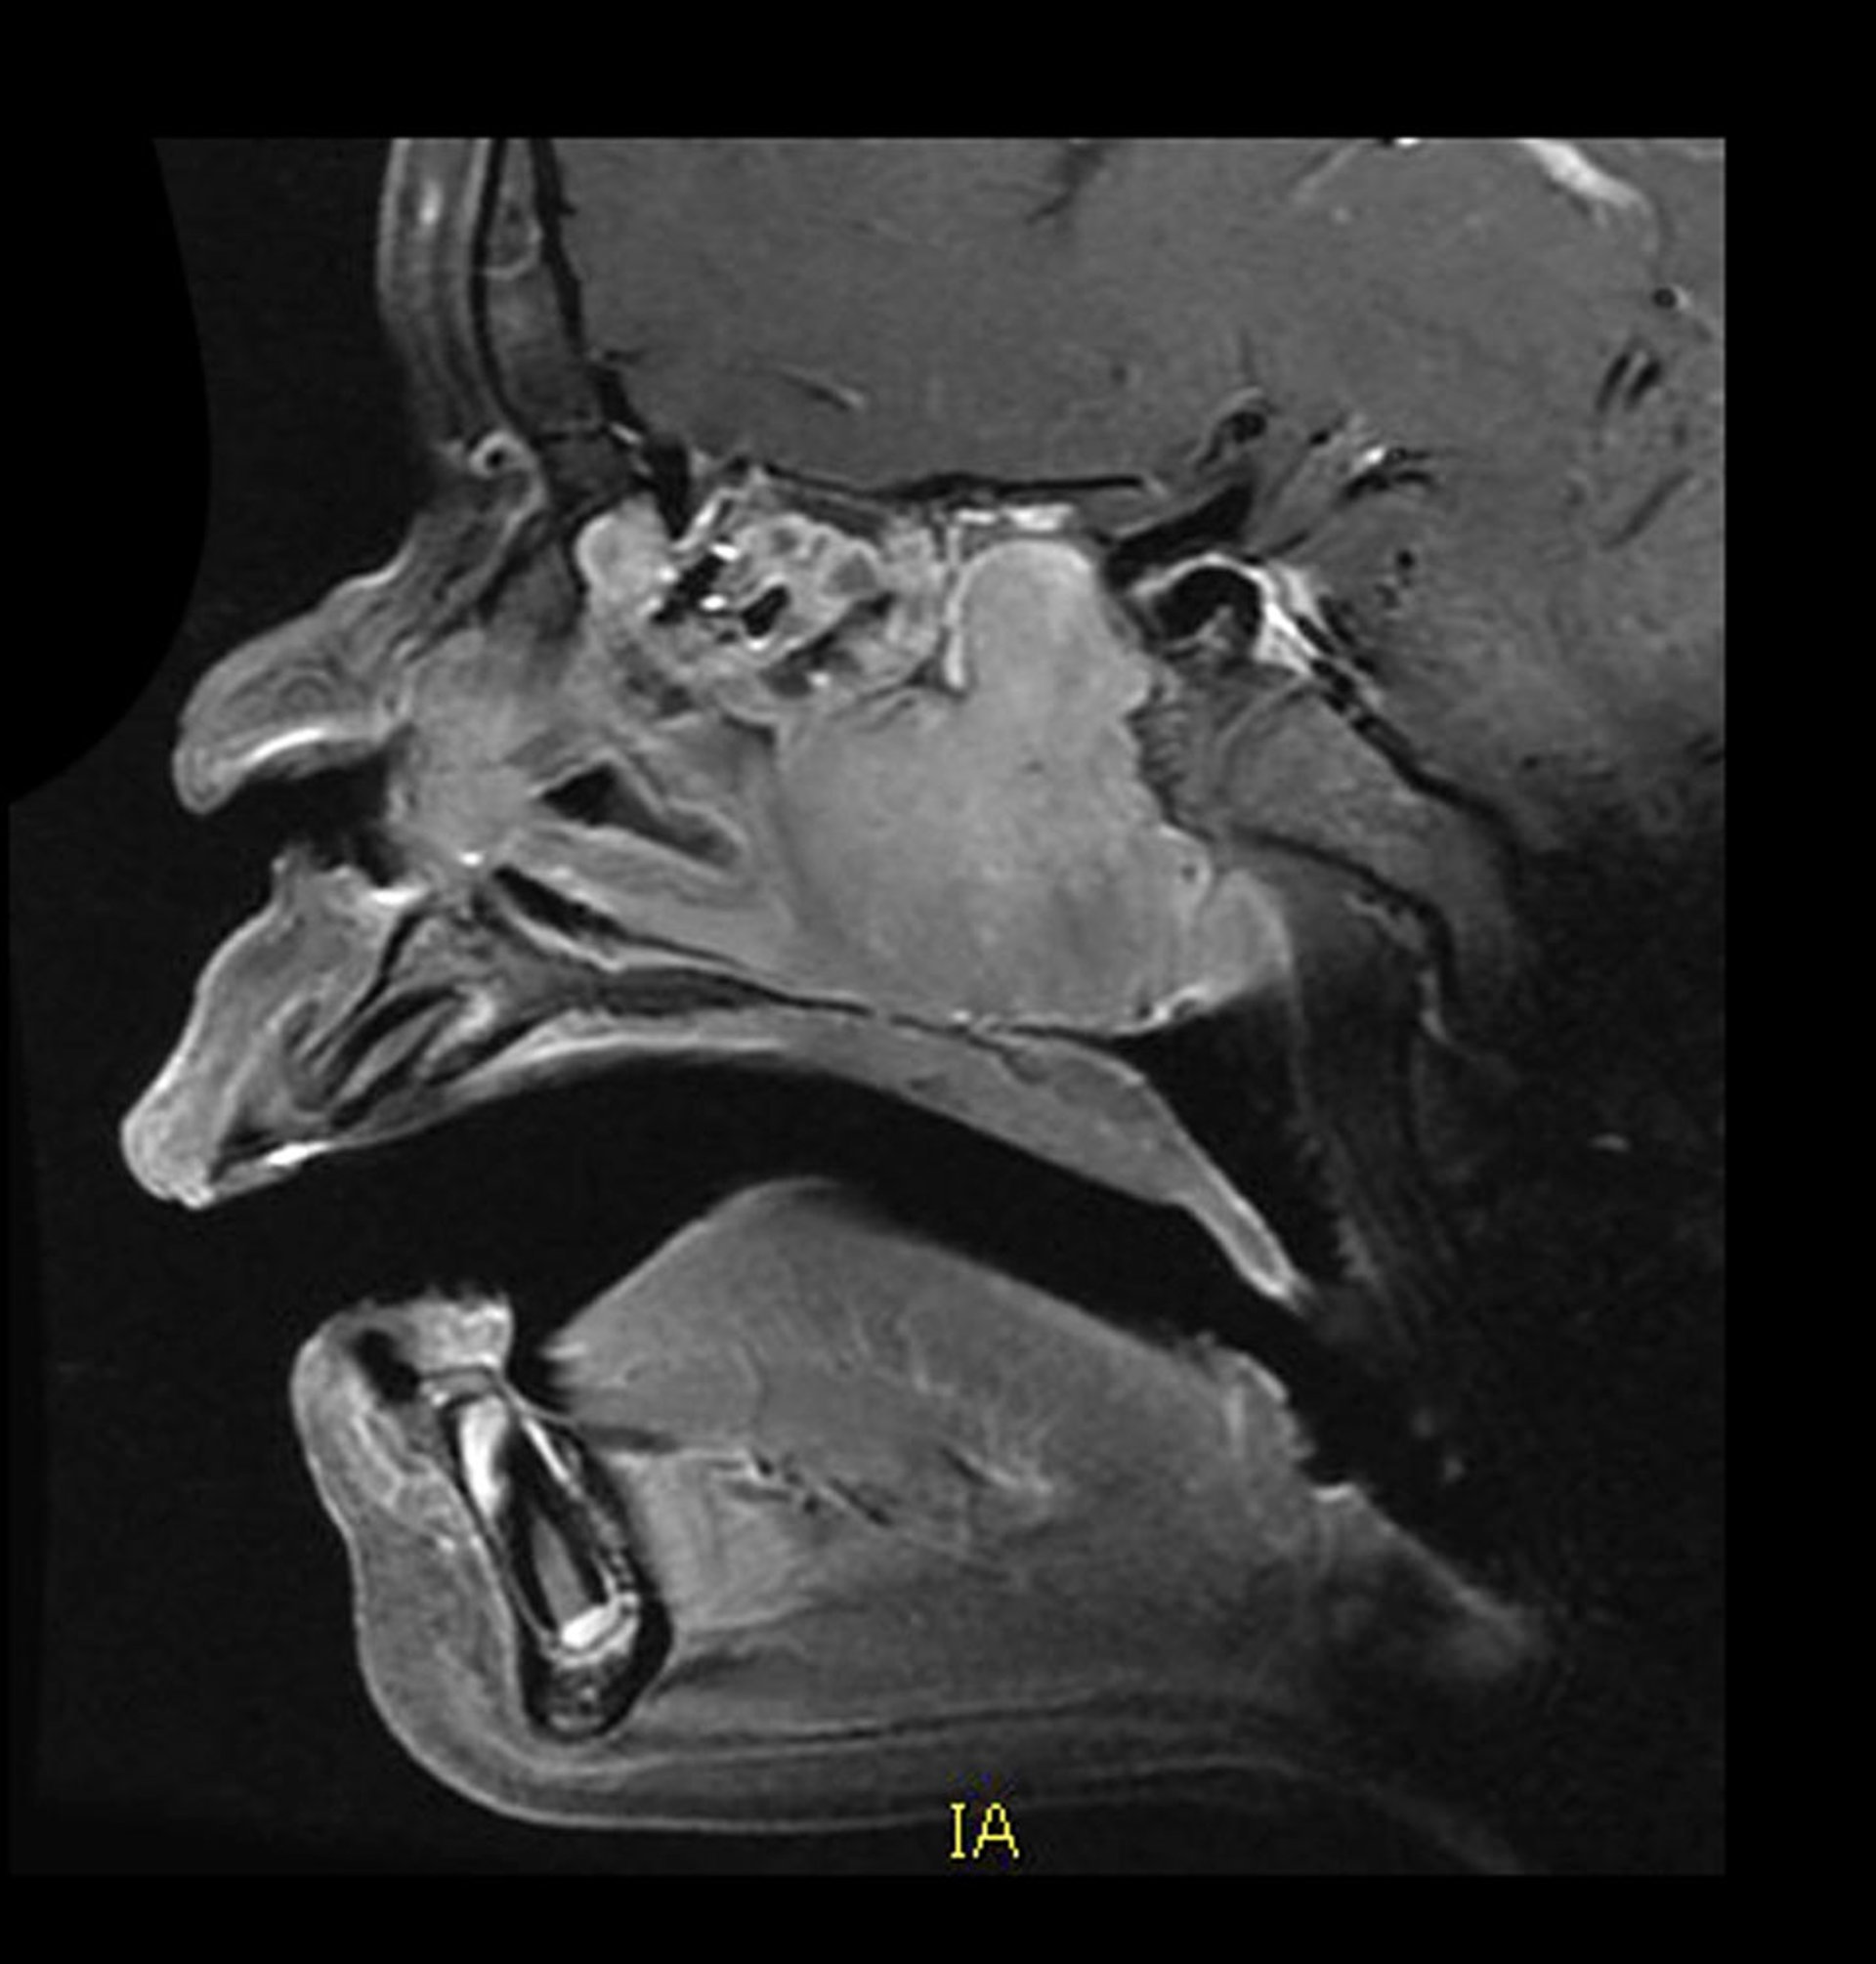

该矢状位增强MRI显示了典型部位和外观的血管性青少年鼻咽血管纤维瘤。后鼻腔可见一均匀强化的肿块,向后生长进入蝶窦。同时还伴有骨质破坏。